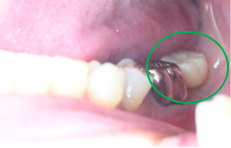

男性Nさん 70代(インプラント)

主訴

右下奥の歯が、グラグラして噛むと痛い。

治療内容

歯根の周りの骨が全く無い状態でしたので、保存することができず抜歯しました。3本歯がないところに2本インプラントを埋入しました。

所感

抜歯後、歯がなくなったところを補う方法には、部分入れ歯とインプラントがあります。この症例の場合、右下以外ほとんど歯が残っていますので、もし部分入れ歯にした場合、入れ歯のところで他のところと同じ感覚で噛むことができないので、慣れることが大変です。また部分入れ歯の支えになっている歯に負担がかかりますので、今後さらに歯を失う可能性が大きくなります。インプラントは、自分の歯と同じ感覚で噛むことができ、単独で植立していますので他の歯に負担がかかることがありませんので、更に歯を失うことを防ぎます。

Before

※赤丸を抜歯しました。